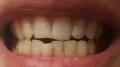

Всегда были ровные зубы, пока не вырос внизу зуб мудрости, который искривил зубы, т.к. мои растут плотно друг к другу. Мне 39, думаю, еще один уже не прорежется.

Что делать в такой ситуации, удалять зуб, потом ставить брекеты? Только на нижнюю челюсть? Можно ли исправить ситуацию без брекетов? Верхние зубы трогать не буду, они идеально ровные.

Да, все правильно, необходимо сначала удалить зуб мудрости и затем установить систему. Обратитесь на очный приём, вам составят план лечения и расскажут подробности.